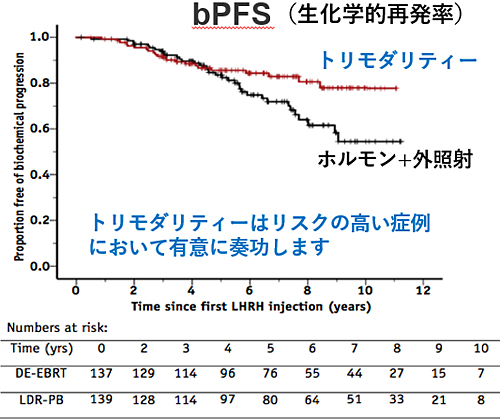

トリモダリティ療法の効果は?

高リスクがんに対する治療効果

現状では高リスクの前立腺がんに対して、最もPSA再発(生化学的再発)が少ないと考えられる治療法です。